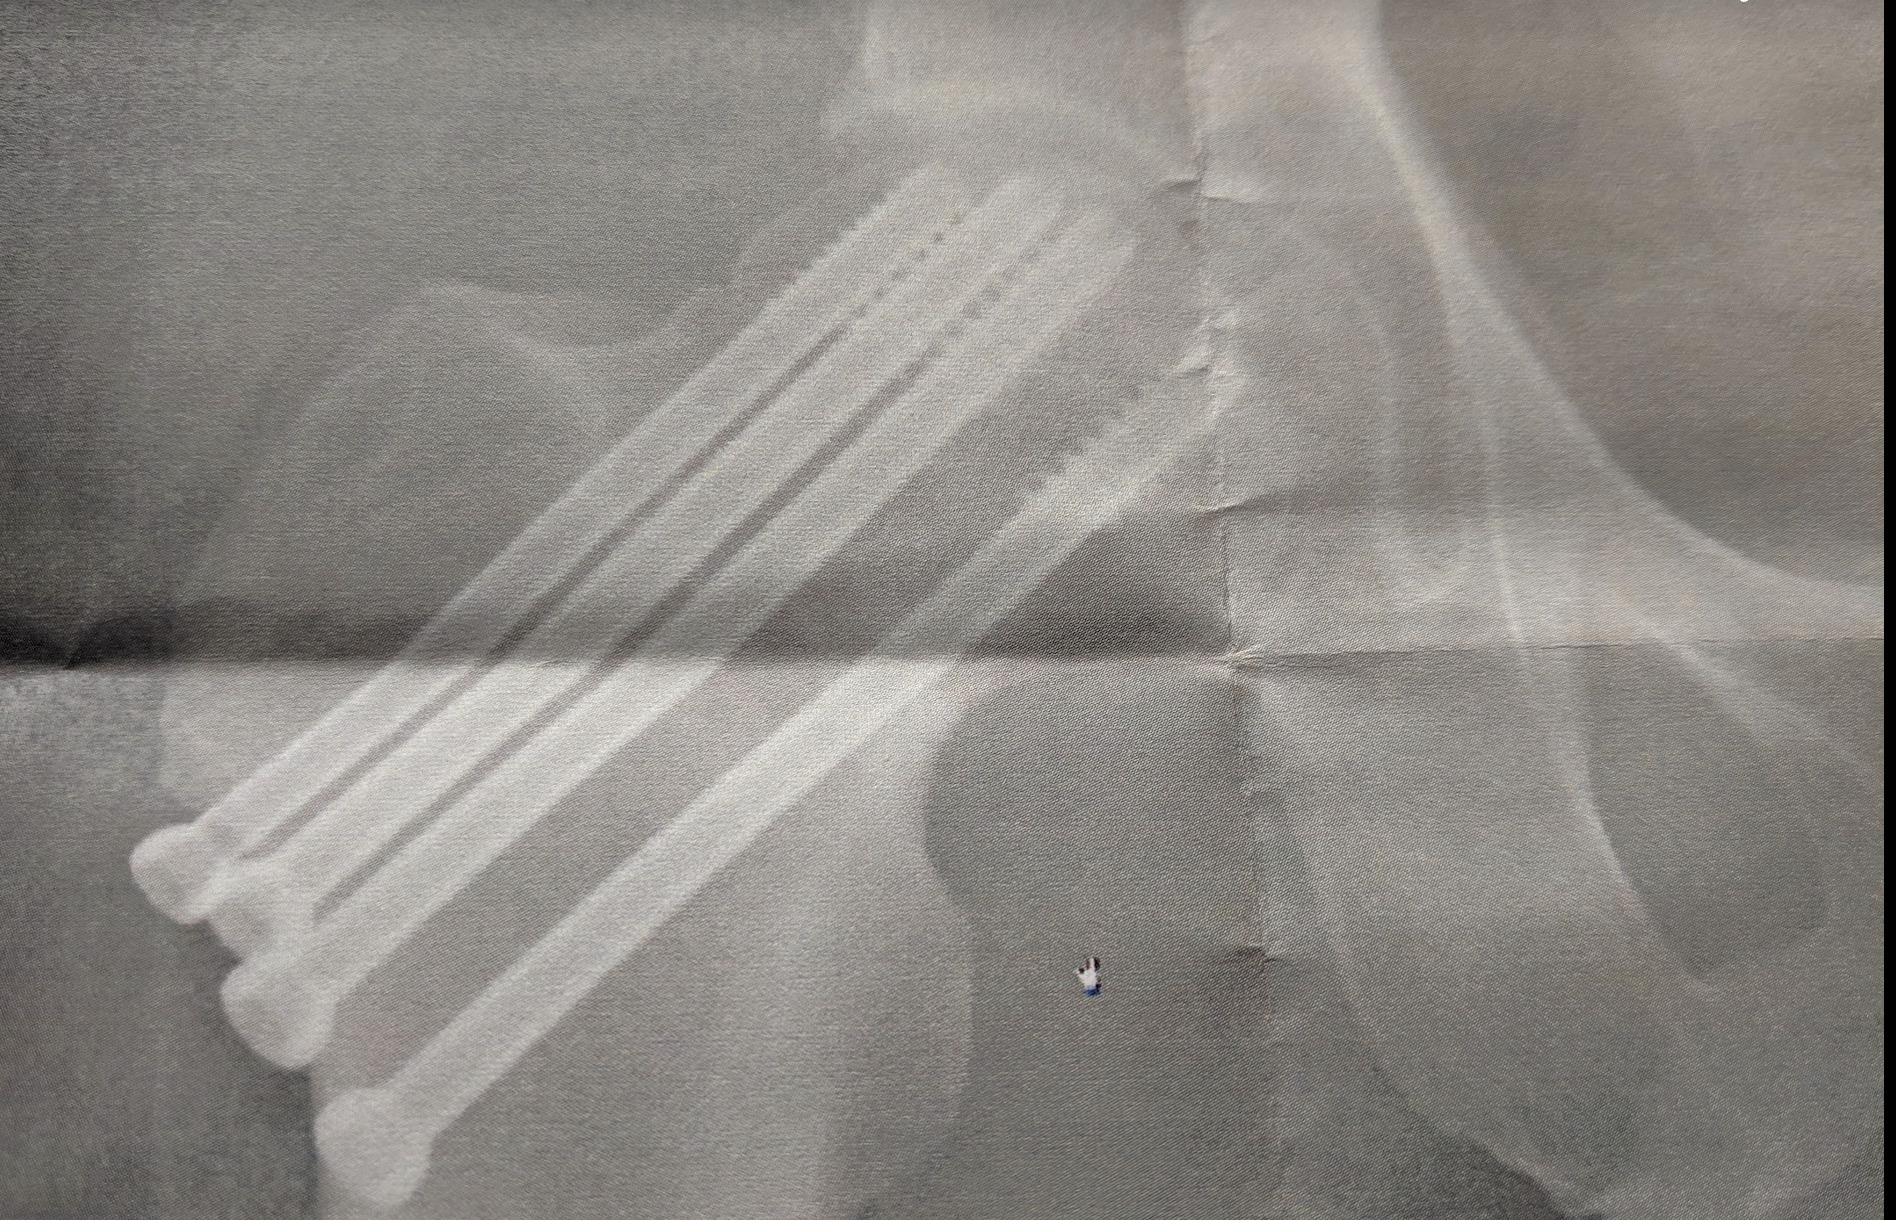

2021年9月に骨折部位をとめていたピンを除去する手術(6日&退院後1ヶ月松葉杖)。

こんなふうにピンで固定して、絶対安静でした。